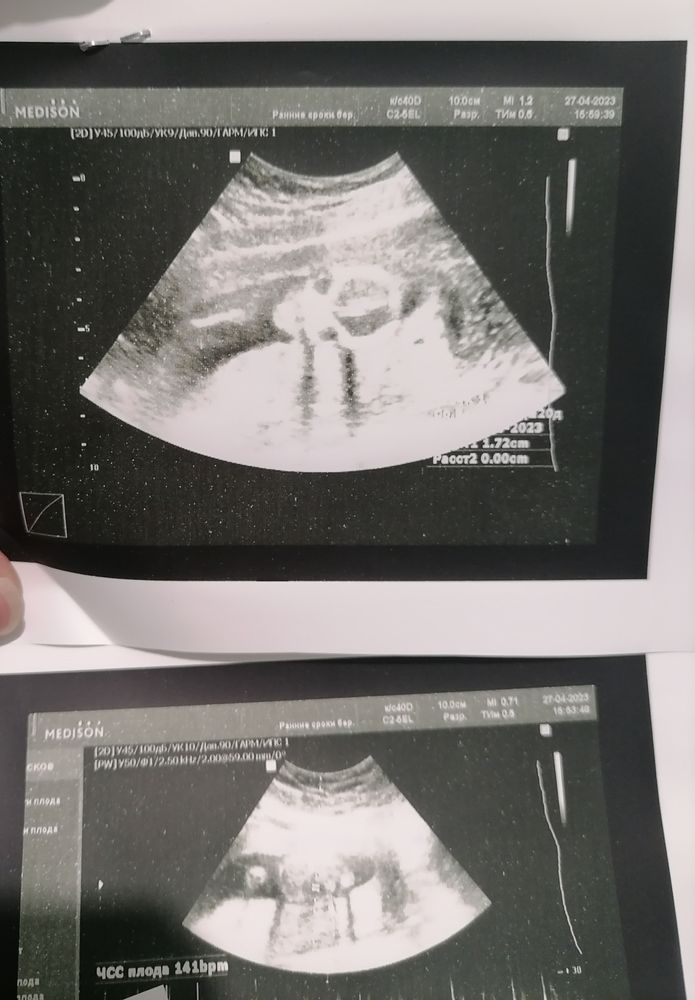

Узи 11,5 неделек 2 скрининг